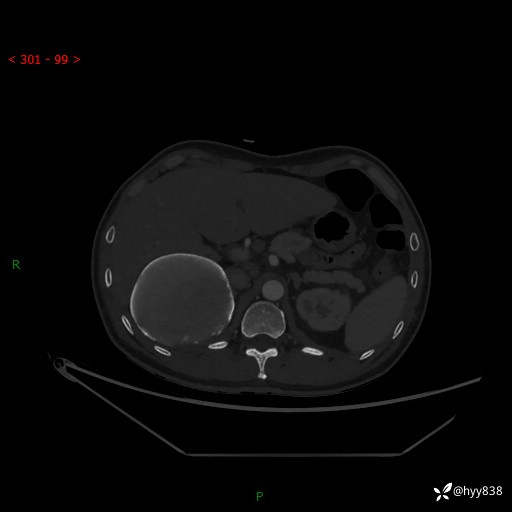

性别:男

年龄:50岁

简要病史:夜尿增多半月,发现肾功能异常1天,超声发现腹膜后占位

腹部CT平扫+增强